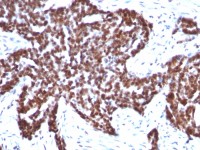

WB, ELISA, IHC

Sumo antibody [4F2.F5.G2]

Sumo 抗体 [4F2.F5.G2]